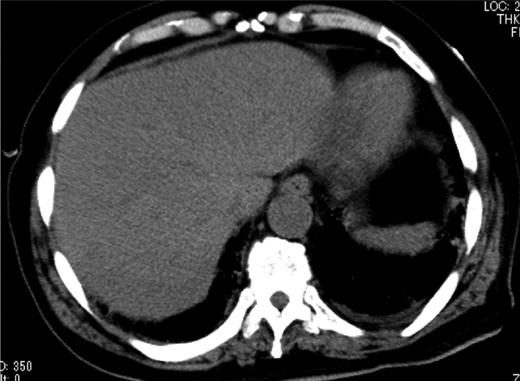

A 79-year-old man with acute abdominal pain had gone to a nearby hospital. As HPVG was detected by abdominal computed tomography (CT), he was transferred to our hospital for further examination and treatment. He had no remarkable past medical history. When he arrived at our hospital, his vital signs were relatively stable (body temperature: 37.2°C; blood pressure: 112/74 mmHg; pulse rate: 68 beats/min). However, physical examination revealed abdominal distention, rebound tenderness and abdominal guarding as signs of peritoneal irritation. The laboratory findings indicated acute inflammation (white blood cell count of 18 400/μL and Creactive protein concentration of 17.7 mg/dL), dehydration and metabolic acidosis (a level of base excess of −7.0 mmol/L). Creatine kinase was remarkably elevated (28 327 IU/L) (Table 1). Plain abdominal radiographs showed distention of the small intestine and suggested subileus (Fig. 1). Contrast-enhanced abdominal CT revealed HPVG (Fig. 2a), a contrast defect in a region of the small intestine, and a small amount of ascites around the intestine. There was no thrombus in any artery; however, the wall of the appendix was moderately thickened when we reevaluated the images retrospectively (Fig. 2b). We performed an urgent laparotomy with the diagnosis of generalized peritonitis caused by intestinal necrosis. A small amount of turbid ascites and a dilated small intestine were observed in the peritoneal cavity. Although the entirety of the small intestine and colon were explored, no intestinal ischemia was detected. Then, we found discoloration of the appendix with wall thickening. We thus made a clinical diagnosis of peritonitis caused by gangrenous appendicitis. Although the appendix wall was fragile, no macroscopic perforation of it was observed. We performed appendectomy and abdominal drainage. Based on the pathological findings, the patient was diagnosed with gangrenous appendicitis, with no evidence of malignancy (Fig. 3). Escherichia coli was positive in the ascitic culture. After the surgery, intravenous antibiotic treatment (meropenem) was administered. The patient subsequently went into septic shock with disseminated intravascular coagulation (DIC). He was therefore admitted to the intensive care unit (ICU), where he received blood purification therapy. The CT images on Day 7 after the surgery showed that HPVG had disappeared (Fig. 4). He left the ICU 7 days after the surgery and was discharged from the hospital another 10 days later.

Gross pathology of the gangrenous appendicitis. Although the appendix wall was markedly thickened and fragile, no macroscopic perforation was observed.